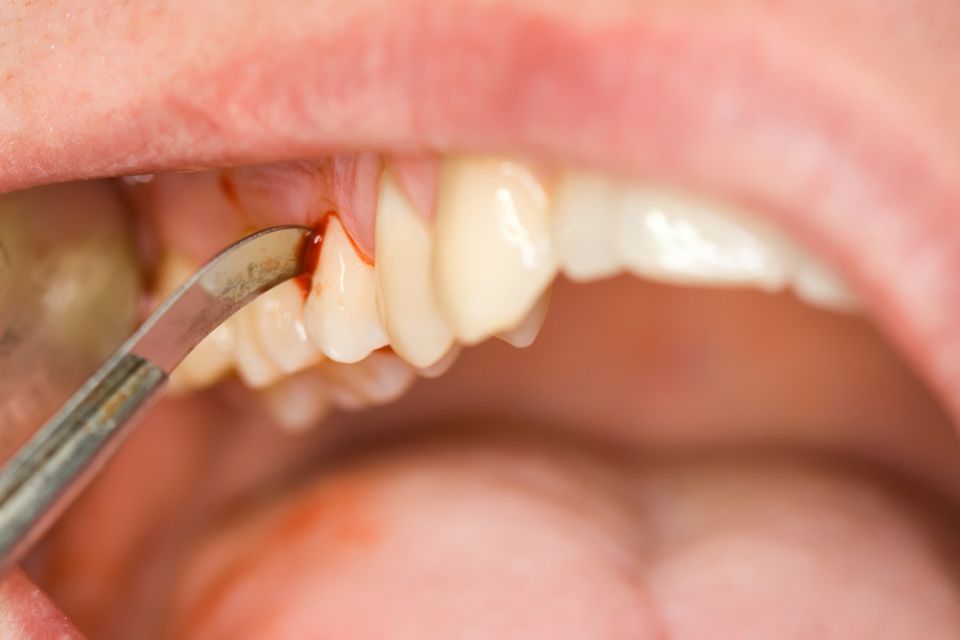

Periodontics and periodontal surgery

Periodontics is the dental specialty dedicated to the study of the periodontium or the supporting structure of the teeth. It encompasses the prevention, diagnosis and treatment of diseases that affect these tissues that surround and attach the tooth to the bone (gingiva, root cement, periodontal ligament and alveolar bone).

Gingivitis that causes inflammation and redness of the gums and possible bleeding when brushing.

Clinically periodontitis presents the signs of gingivitis but is also accompanied by the loss of the tissues that support the tooth: the periodontal ligament and the alveolar bone, causing the mobility of the tooth and future loss of it if it is not treated.

Gingival recession is not a disease itself but rather a morphological disorder where the recession of the marginal gingiva can present aesthetic problems and discomfort due to the sensitivity produced by the exposure of the dental necks. The most frequent causes are due to incorrect brushing, functional overload or due to untreated chronic periodontitis.

Sometimes we cannot treat periodontitis only with conservative treatment and we must resort to surgical techniques to achieve better results, for example with periodontal surgery.

There are other types of surgical interventions at the level of the gums and oral mucosa such as: gingivectomies / gingivoplasties and crown lengthening that serve to save compromised teeth or to achieve aesthetic changes in the smile. Another example would be mucogingival surgery used to cover recessions, to gain volume of the soft tissues of the period of the tooth or to achieve a stronger and healthier gum around teeth or implants.